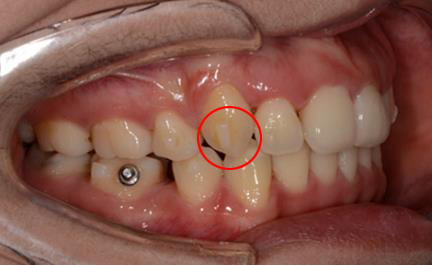

(2) 钢丝扎嘴(结扎丝与弓丝):若为结扎丝扎嘴,可以采用圆钝物体比如筷子、铅笔头等将结扎丝重新压到弓丝的下方,操作过程中力量不要过大,避免托槽松动脱落。若为主弓丝扎嘴,则建议使用粘膜保护蜡或口香糖包裹扎嘴部位(如上图所示)。